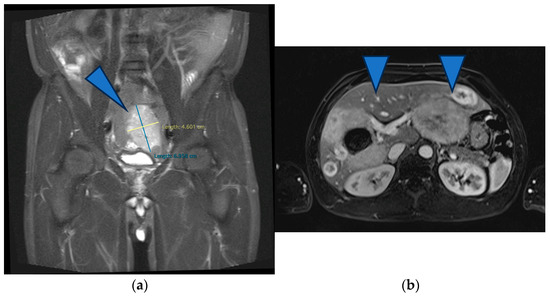

The patient was referred to our tertiary hepato-bilio-pancreatic surgery center to reassess GLM resectability. At this point, the patient was handicapped due to the giant metastases impeding walking and breathing; the ECOG performance status was 4, and the Charlson comorbidity index was 6. At imaging, aside from several small metastases in the central part of the liver (liver segments 4, 5, and 8), there were two large groups of confluence metastases: One was 17/10 cm in size, completely occupying segments 6 and 7, partly occupying segments 5 and 8, and invading the right hepatic vein. The other was 14/11 cm in size, occupying the entirety of segment 2, partly occupying segments 3 and 4 superior, and invading the left hepatic vein (Figure 4). Total liver volume was 5092 cm3; left hemiliver volume was 1876 cm3, while right hemiliver volume was 3217 cm3.

Figure 4.

MRI showing the two groups of large liver metastases: (a) one group located in segments 6 and 7 and partly in segments 5 and 8, invading the right hepatic vein, while (b) the other occupied the entirety of segment 2 and partly occupied segments 3 and 4 superior, invading the left hepatic vein.